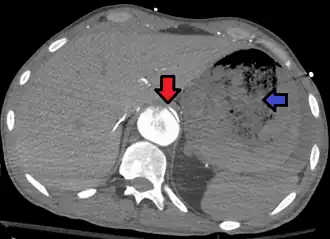

![]() Fístula arortoentérica y disección aórtica de la aorta torácica. La flecha indica la solapa en la aorta. La heterogeneidad es sangre en el estómago. | ||

Una fístula aortoentérica es una conexión anormal[1] entre la aorta y los intestinos, el estómago o el esófago. Por aquí puede haber una pérdida significativa de sangre que es acumulada en los intestinos lo que produce heces con sangre y la muerte.[2] Por lo general, es secundaria a una reparación de aneurisma aórtico abdominal. La tercera o cuarta porción del duodeno es el sitio más común para la formación de fístulas aortoentéricas, seguida del yeyuno y el íleon.